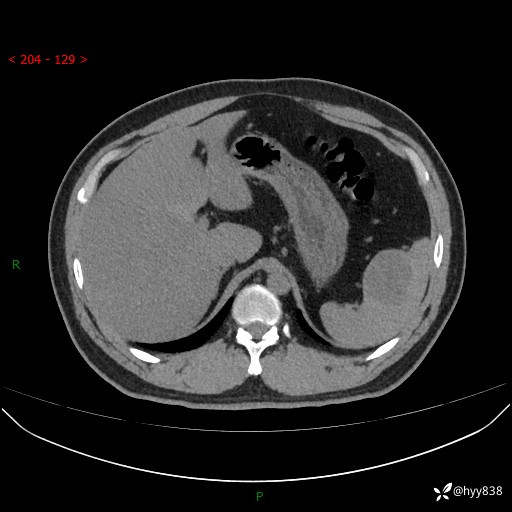

【患者信息】:31岁/男

【主诉】:超声发现脾脏肿物,为进一步诊治来我院,门诊以“脾脏占位”收入院

【检查】:上腹部CT平扫+增强